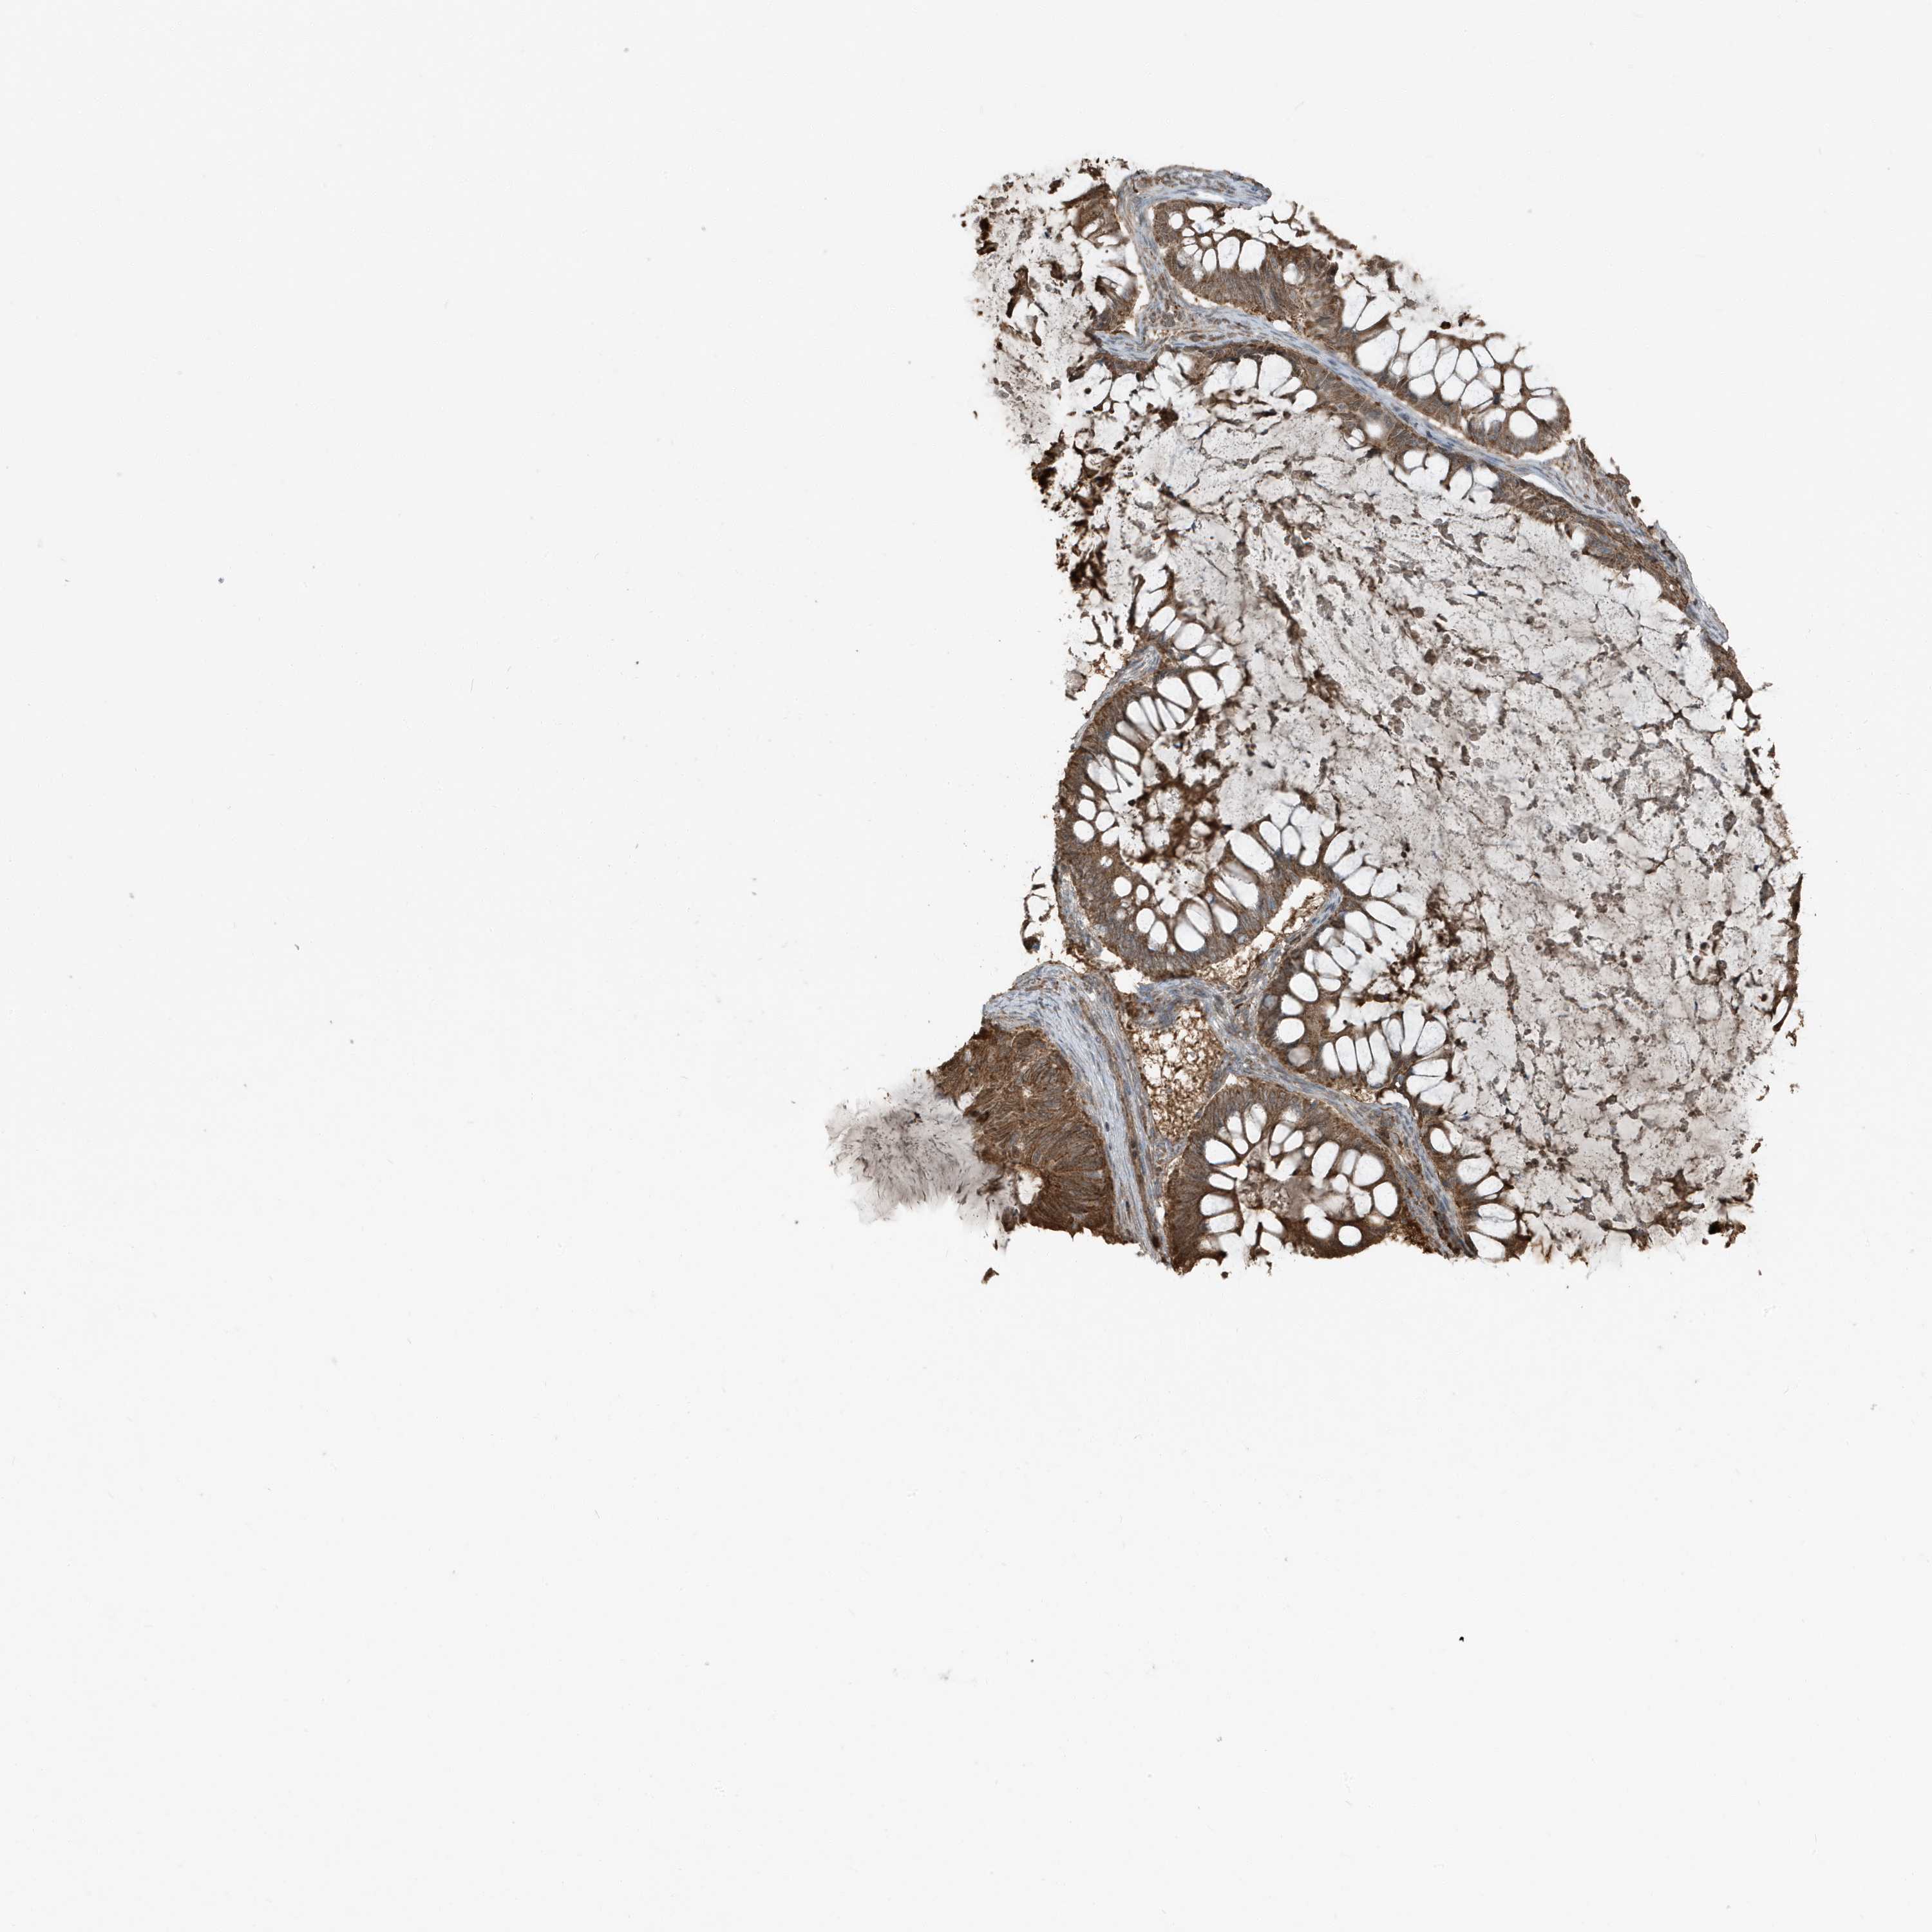

OVARIAN CANCER - Protein expressioni

A mouse-over function shows sample information and annotation data. Click on an image to view it in a full screen mode. Samples can be filtered based on level of antibody staining by selecting one or several of the following categories: high, medium, low and not detected. The assay and annotation is described here.

Note that samples used for immunohistochemistry by the Human Protein Atlas do not correspond to samples in the TCGA dataset.

Antibody stainingi

Antibody staining in the annotated cell types in the current human tissue is reported as not detected, low, medium, or high, based on conventional immunohistochemistry profiling in selected tissues. This score is based on the combination of the staining intensity and fraction of stained cells.

Each image is clickable and will lead to virtual microscopy that enables deeper exploration of all samples and also displays staining intensity scores, fraction scores and subcellular localization as well as patient and tissue information for each sample.

Antibody HPA035258

Staining

High

Medium

Low

Not detected

Intensity

Strong

Moderate

Weak

Negative

Quantity

>75%

75%-25%

<25%

None

Location

Nuclear

Cytoplasmic/membranous

Cytoplasmic/membranous,nuclear

Cystadenocarcinoma, serous, NOS

Carcinoma, endometroid

Cystadenocarcinoma, mucinous, NOS

Carcinoma, NOS